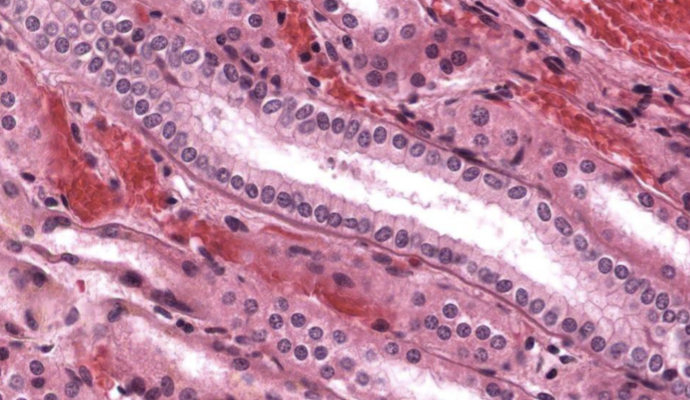

pseudoestratificado